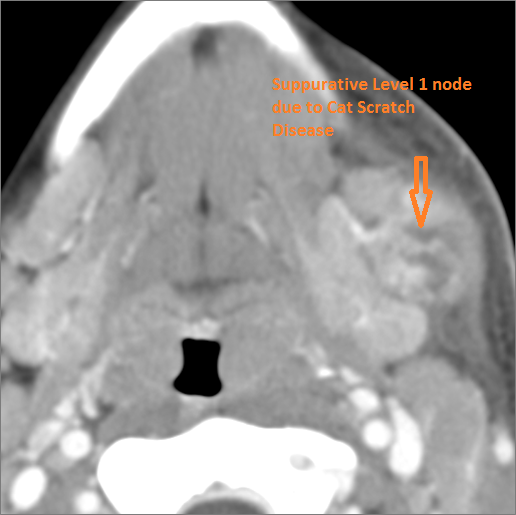

9 month old male presenting to the emergency room with poor feeding, fever, respiratory distress and possible retropharyngeal abscess or suppurative retropharyngeal adenitis.Exam

There is reactive cervical lymphadenopathy. |

Yes | NA |

There is suppurative cervical lymphadenopathy. |

No | NA |

Pharyngitis with suppurative retropharyngeal adenitis.